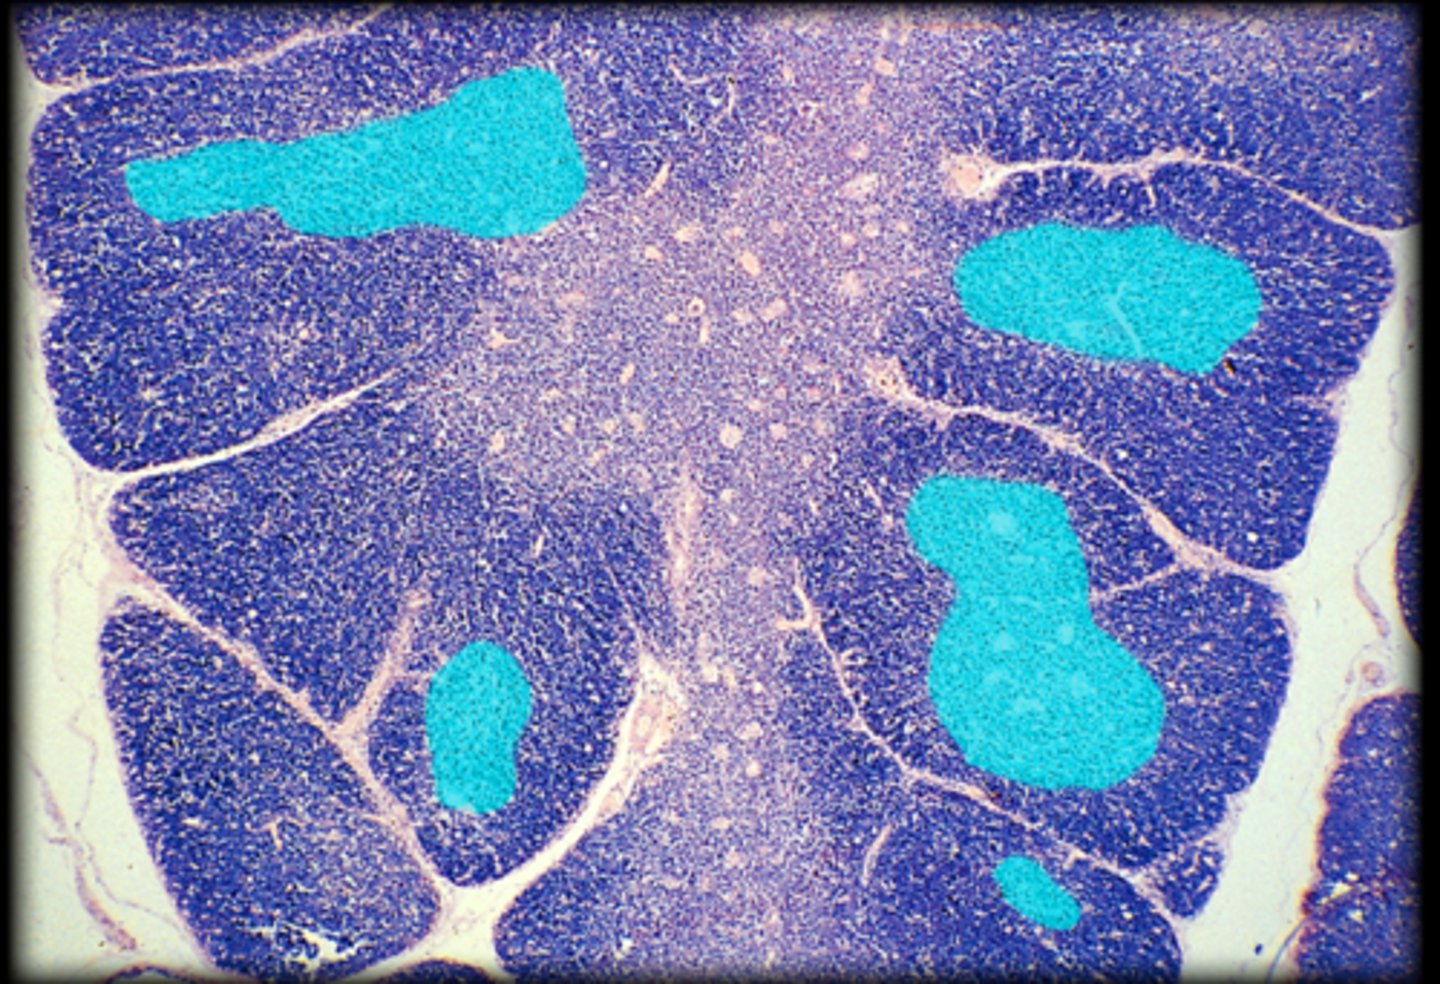

cortex

Fetal thymus

medulla

hassall's corpuscle

Thymus